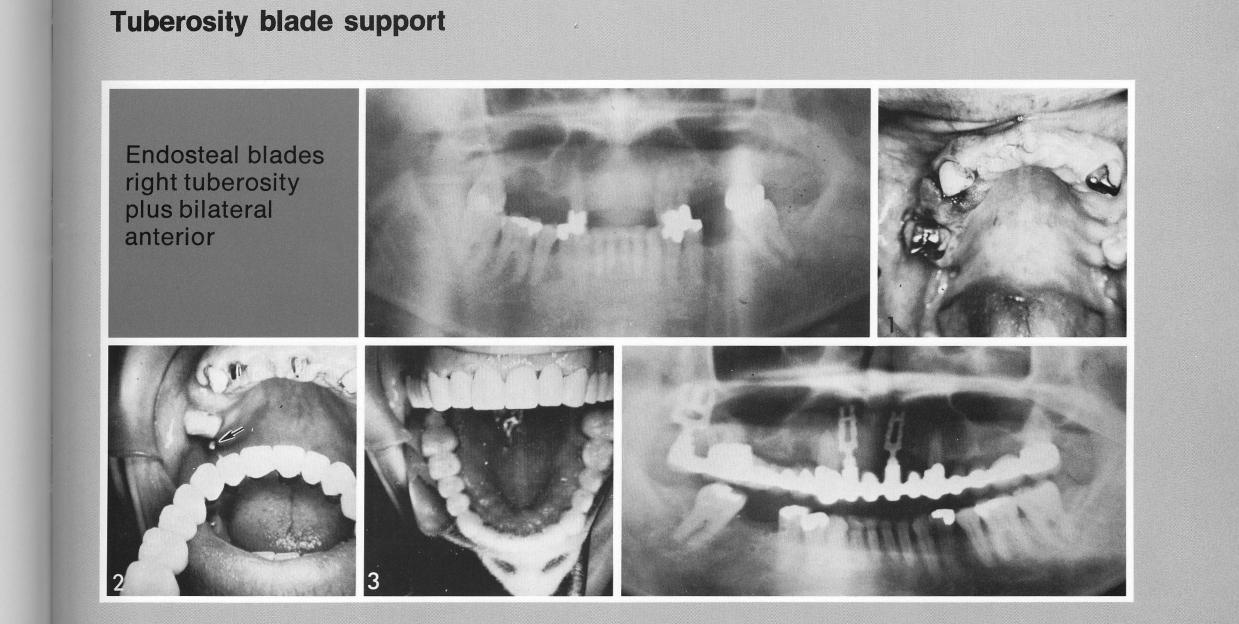

Additional support for a full-arch restoration was needed in an arch with few remaining teeth (1). Single-tooth bladevents were inserted anteriorly between the cuspids, and a single bladevent was seated in the right tuberosity to lessen the burden on the first molar (2). The finished restoration has a third molar crown over the tuberosity bladevent.

Tuberosity blade support

1 Single maxillary tooth bladevent implant seated in tuberosity region